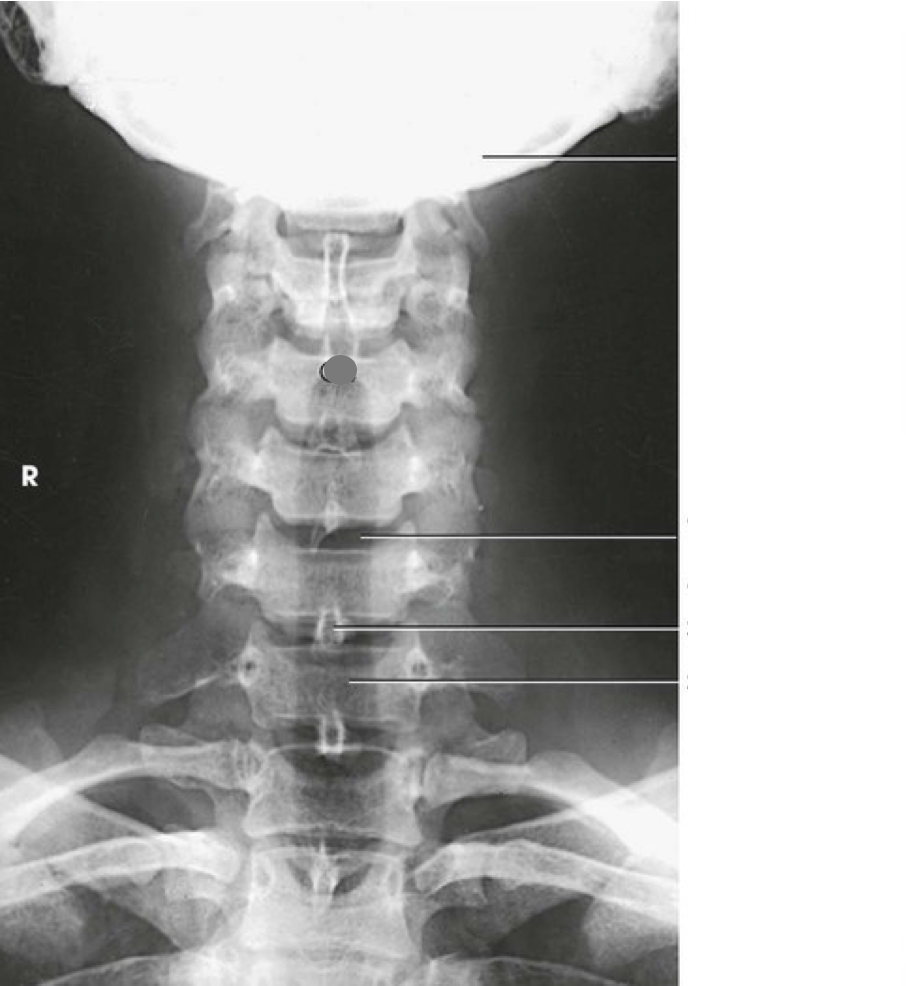

Question 1

Question

Label the image

Image:

Answer

occipital bone

occlusal surface of teeth

dens

mandibular ramus

lateral mass of atlas

inferior articular process of atlas

spinous process of axis